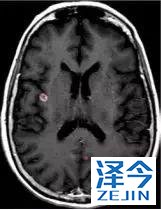

一位77岁的女性患有EPS15-NTRK1 IV期非小细胞肺癌,我们可以看到她的双肺满是病灶,并且出现了肝脏和脑转移,可以说是非常非常晚期了,

脑转移病变显示缩小了95%!

初始, 2018年6月 3周期 2018年8月